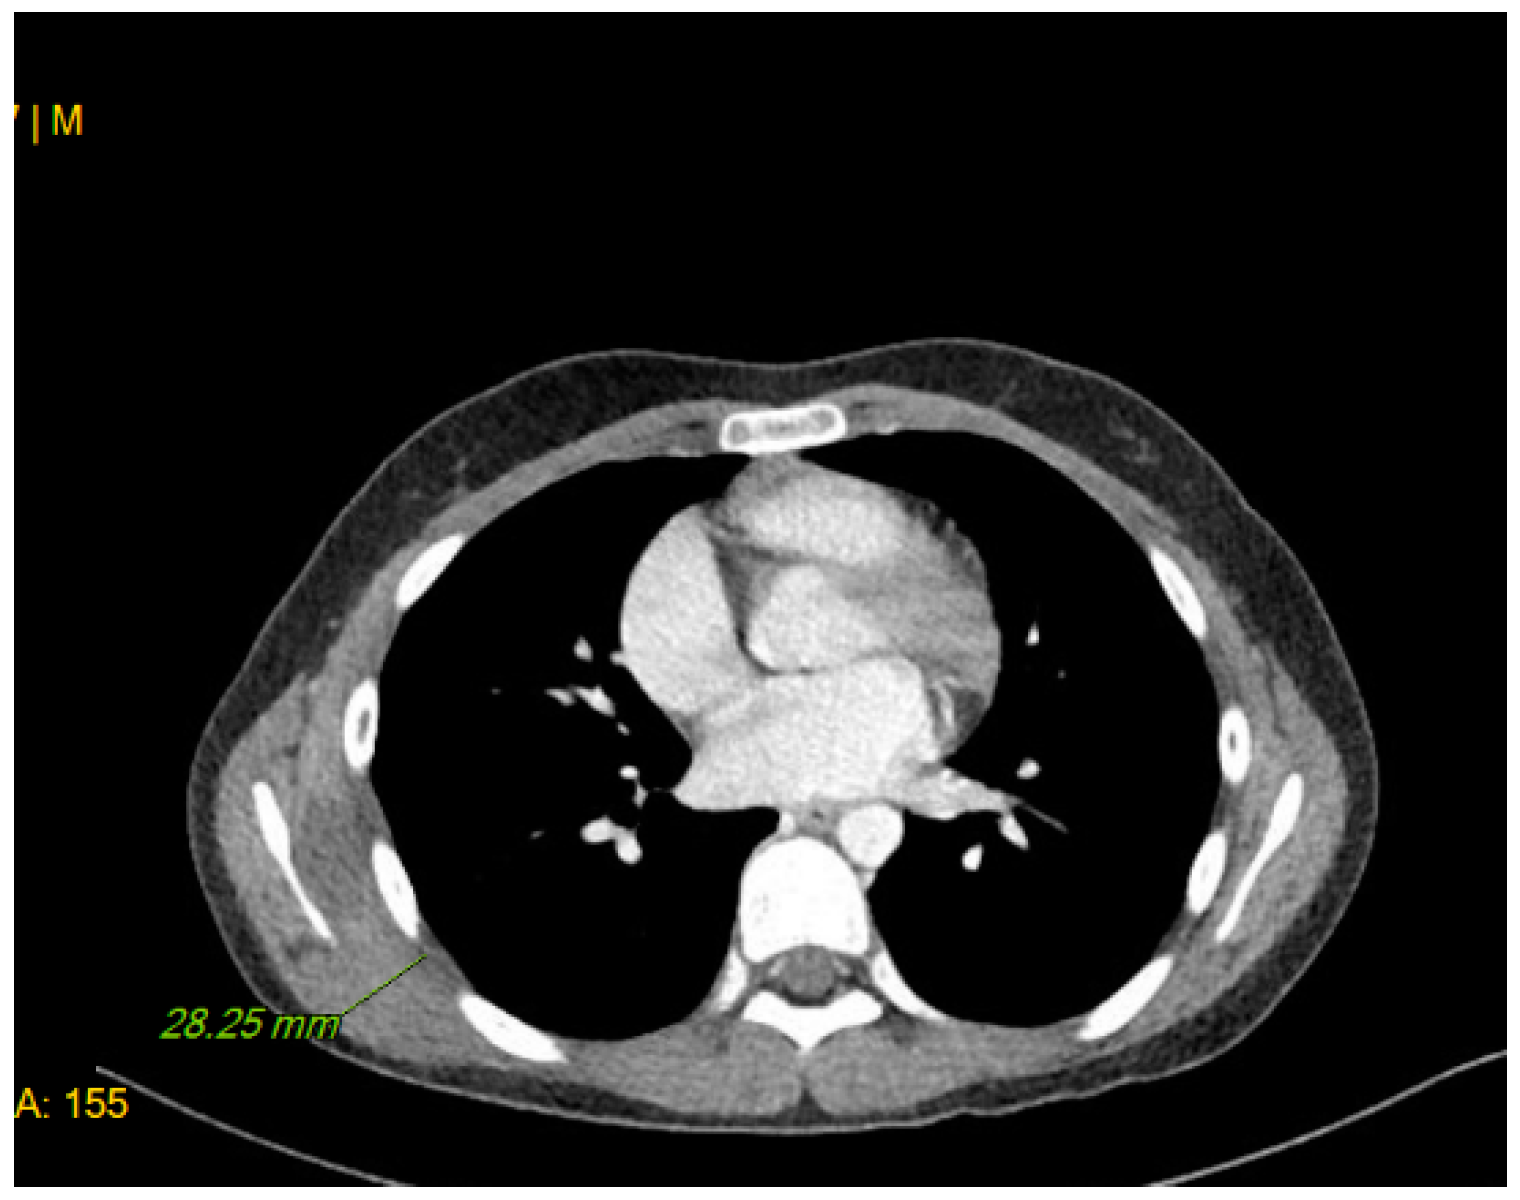

2. Case Description